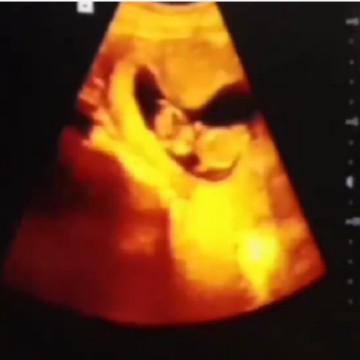

usg uk 12w 4d

Bundaa kmrin minggu aku habis usg yg pertama kali dalam hidupku? dann speacless banget liht dedek nyaa aktif, gerak2 yaa meskipun aku nya blm bisa merasakan pergerakannya, tapi lihat di layar usg tuuh rasa bahagiaaa yg tak ternilai, berat debaynya 6,1gr